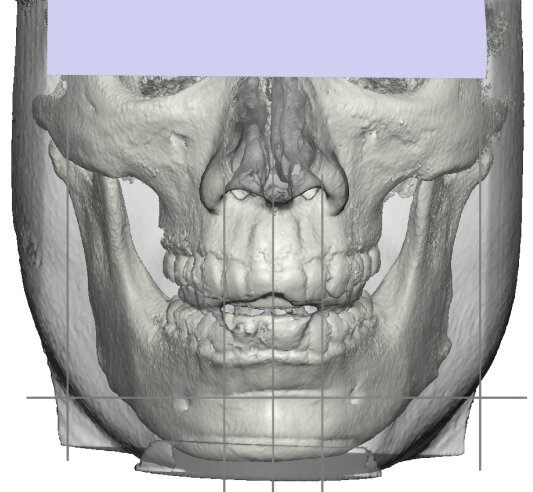

Recently got this implant design from Dr. Y for custom mandible (jaw & chin) and malar / cheekbones with infraorbital rims.

@zeek The design says they are ~5.5 at the most prominent point I believe. Also, I consider my cheekbone area much better than average - Dr. Y himself said 'You know your malar area isn't as bad as you think'. That in conjunction with the fact I provided pictures of Toni Mahfud and Mario Rodriguez as reference makes me confident that his design will be plenty. He also gave me the impression that he was doing a bit 'more' with my particular design and that the result will be spot on with the Mahfud & Rodriguez look. Love the design, it's like a fusion of both Mahfud's and Rodriguez's midface and lower-third.